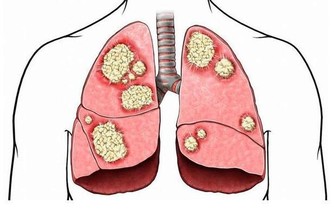

至於要看一個人到底能不能用,還是需要看收益和風險誰更大一些,阿司匹林用於疾病的預防,主要好處是能夠減少非致死性缺血事件,

主要風險是來自於顯著增加非致死性大出血的事件,其中包括胃腸道出血和顱內出血等等。